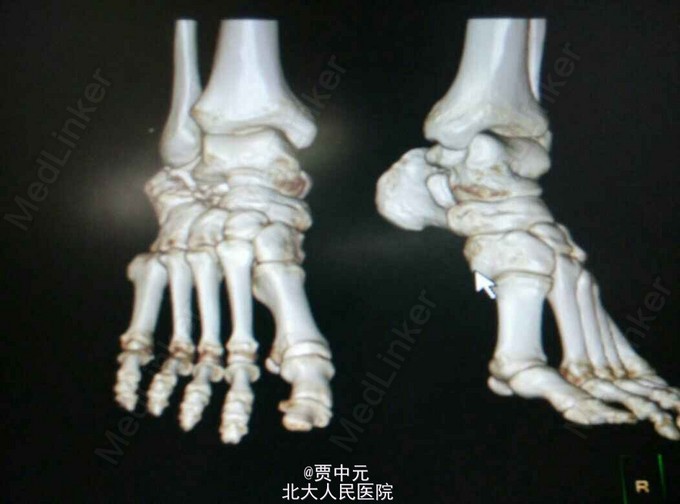

男性,31岁,主因“高处坠落伤致右足跟部疼痛,活动受限1天”于急诊以“右侧跟骨骨折”收入院。 一.病例特点 1.青年男性,高处坠落史。 2.患者约1天前自高处坠落右足着地,当时未昏迷,自觉右足肿痛,不敢活动,在当地医院拍片示:右侧跟骨骨折,为进一步手术治疗收住院。自入院来,患者无发热及胸闷憋气及腹痛症状

入院查体:右足跟部肿胀,局部皮下淤血,压痛,叩击痛,趾端血运可,足趾感觉及活动可,余肢体未见明显异常。 X线:右侧跟骨骨折(外院)

右侧跟骨骨折:高处坠落伤1天,查体:右足跟部肿胀,局部皮下淤血,压痛,叩击痛,趾端血运可,余肢体未见明显异常。 X线:右侧跟骨骨折(外院),根据外伤史,查体及X线检查,故此诊断明确

入院后考虑患者伤足局部软组织损伤重,皮肤条件欠佳,予以消肿,待皮纹征阳性后于今日在椎管内麻醉下行右跟骨骨折切开复位植骨内固定术。